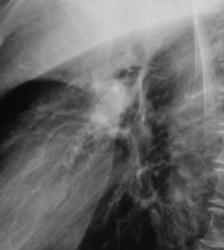

На иллюстрациях 1, 2. Представлены флюорограммы, произведенные в «настоящее время». На флюорограмме, произведенной в прямой стандартной проекции, визуализируется снижение прозрачности легочной ткани верхней доли правого лёгкого однородной структуры, без четких контуров. Правый корень несколько подтянут кверху, что навело на мысль об ателектазе. На боковой флюорограмме дифференцируется снижение прозрачности верхней доли средней интенсивности, однородной структуры с четкими «вогнутыми контурами», имеет место уплотнение структур корня с «кажущейся тяжистостью» кпереди, в средней доле. В грудном отделе позвоночника явления межпозвонкового остеохондроза.